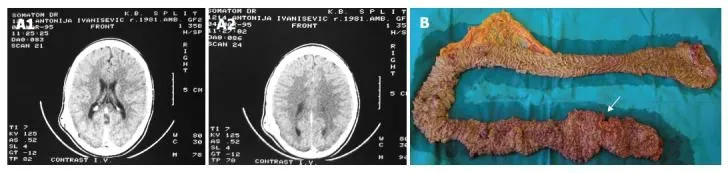

Рис. 1. Синдром Гарднера [10].

А. На компьютерной томограмме с контрастным усилением визуализируется остеома левой височной области.

В. На макропрепарате толстой кишки после колопроктэктомии видны множественные полипы преимущественно в сигмовидной и прямой кишке. Стрелкой указана локализация рака прямой кишки.